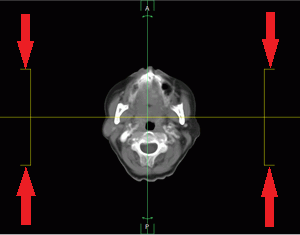

In the MIP, MinIP and AIP render modes, the slice thickness is set using the Thickness PIC button on the toolbar. Click the button and select the predefined values from the list, or click the User defined button to specify your own value. In the projection window, the slice borders are marked by lines (the red arrows in Fig. 5.24).

To set the thickness of solely the slice which is projected on a sertain plane, move the cursor to any line, marked by the arrows in Fig. 5.24, for the corresponding slice and move it, holding the left mouse button.

PIC

Figure 5.24: Slice borders